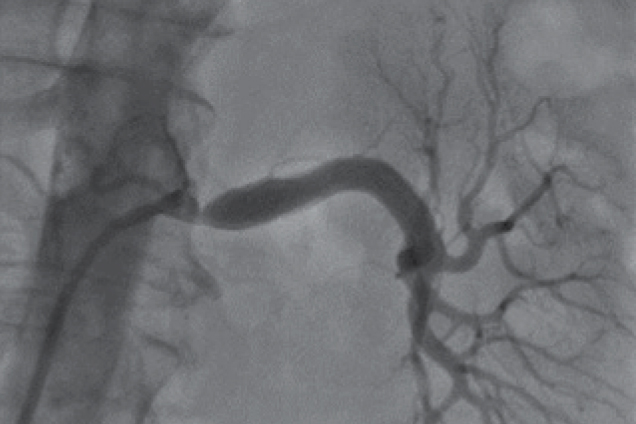

Kissing Stent deployment for aortoiliac occlusive disease with Advanta V12

Bilateral iliac artery occlusion

Bilateral Iliac artery occlusion - pre restoration

Pre treatment

Bilateral Iliac artery occlusion - post restoration

Post treatment

Restoration of lumen diameter with Advanta V12 Kissing Stents. 10 x 38 mm Advanta V12 in the RIA; 10 x 59 mm Advanta V12 stents overlapped in LIA.

RIA - Right Iliac Artery, LIA - Left Iliac Artery